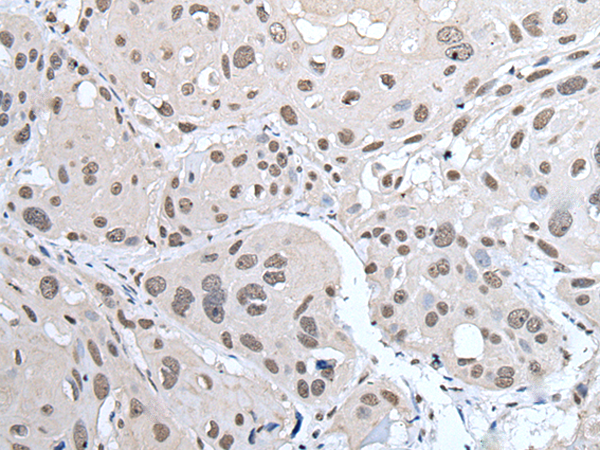

分类: 科研抗体货号: P08648别名: S4; p56; P26S4应用: WB,IHC反应种属: Human, Mouse, Rat